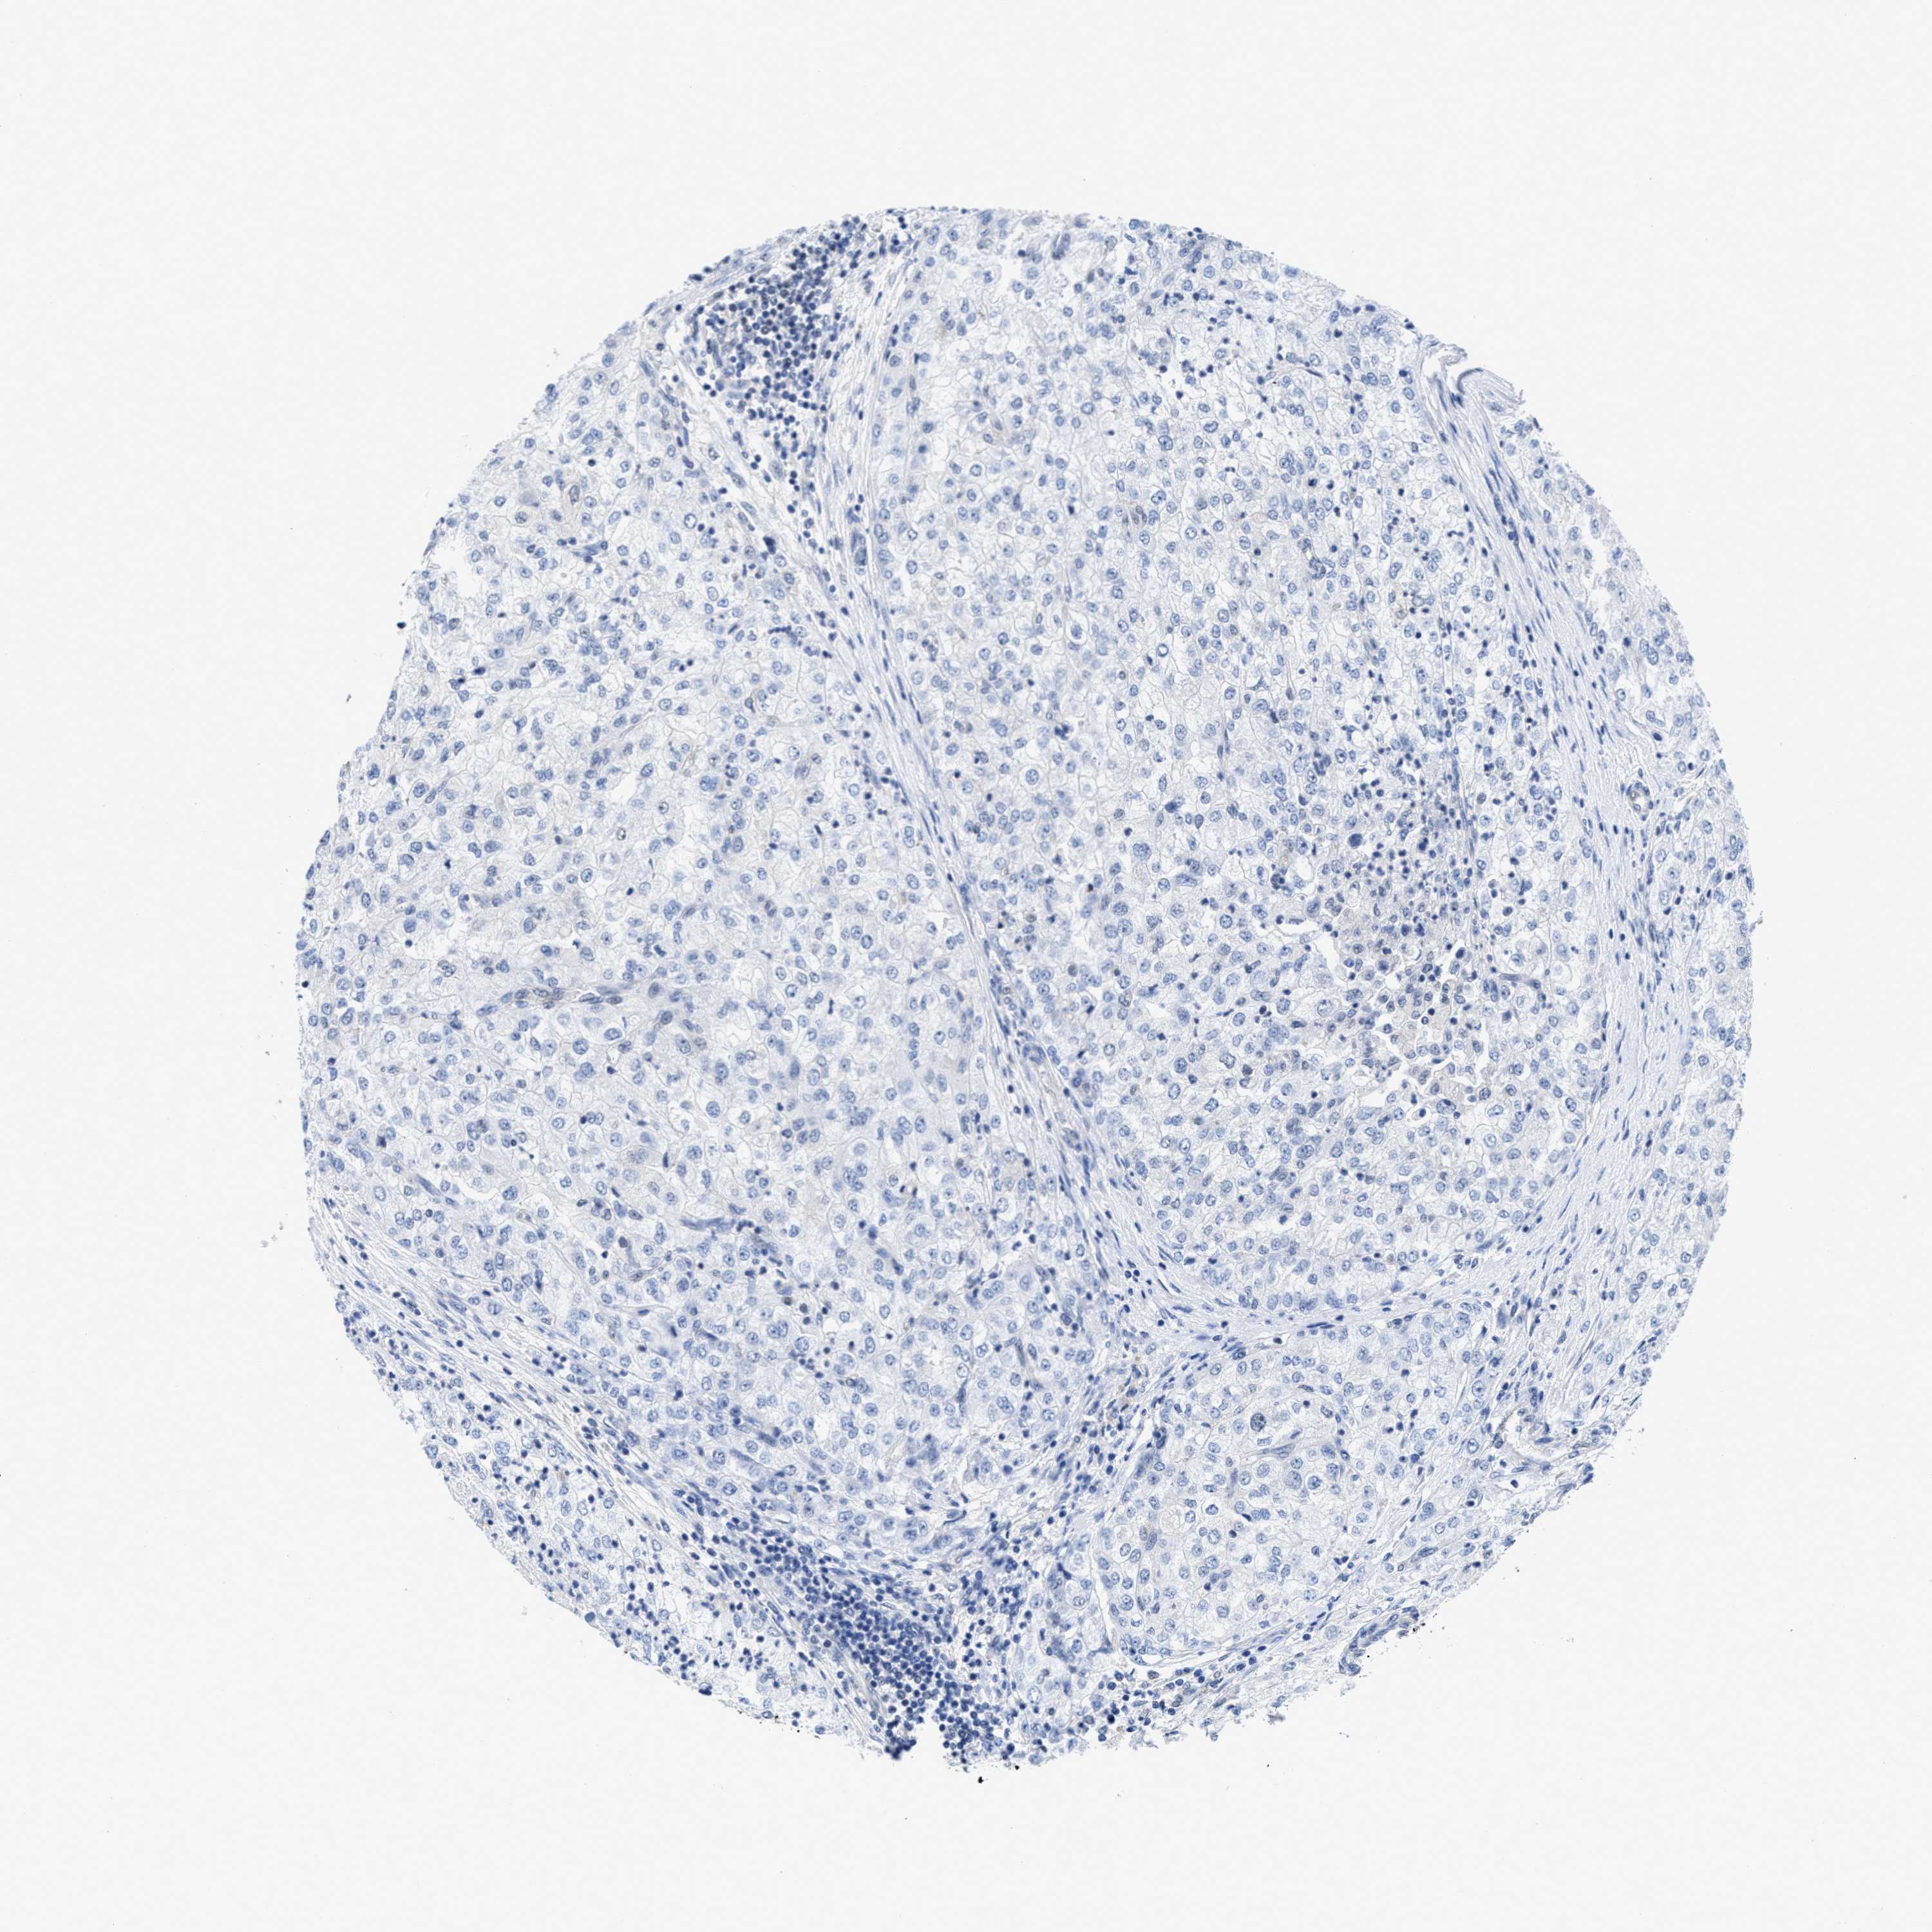

KIDNEY RENAL CLEAR CELL CARCINOMA (VALIDATION) - Interactive survival scatter ploti

The Survival Scatter plot shows the clinical status (i.e. dead or alive) for all individuals in the patient cohort, based on the same data that underlies the corresponding Kaplan-Meier plots. Patients that are alive at last time for follow-up are shown in blue and patients who have died during the study are shown in red.

The x-axis shows the expression levels (FPKM) of the investigated gene in the tumor tissue at the time of diagnosis. The y-axis shows the follow-up time after diagnosis (years). Both axes are complimented with kernel density curves demonstrating the data density over the axes. The top density plot shows the expression levels (FPKM) distribution among dead (red) and alive patients (blue). The right density plot shows the data density of the survived years of dead patients with high and low expression levels respectively, stratified using the cutoff indicated by the vertical dashed line through the Survival Scatter plot. This cutoff is automatically defined based on the FPKM cutoff that minimizes the p-score. The cutoff can be changed by dragging the vertical line or by entering a cutoff value in the square labeled "Current cut-off".

Under the Survival Scatter plot the p-score landscape (black curve; left axis) is shown together with dead median separation (red curve; right axis). Dead median separation is the difference in median mRNA expression between patients who have died with high and low expression, respectively. It is calculated as follows: median FPKM expression of dead patients with high expression - median FPKM expression of dead patients with low expression. This is intended to aid the user in visually exploring custom cutoffs and the associated p-scores and dead median separation.

Individual patient data is displayed and can be filtered by clicking on one or more of the category buttons on the top of the page. Categories describing expression level and patient information include: high, low, alive, dead, female, male and tumor stages. The scale of the x-axis can be toggled between linear and log-scale by clicking on the "x log" button. Mouse-over function shows TCGA ID, patient information and mRNA expression (FPKM) for each patient.

& Survival analysisi

Kaplan-Meier plots summarize results from analysis of correlation between mRNA expression level and patient survival. Patients were divided based on level of expression into one of the two groups "low" (under cut off) or "high" (over cut off). X-axis shows time for survival (years) and y-axis shows the probability of survival, where 1.0 corresponds to 100 percent.

ACLY is not prognostic in Kidney Renal Clear Cell Carcinoma (validation)

: 169.05

Average pTPM 211.9

Number of samples 100